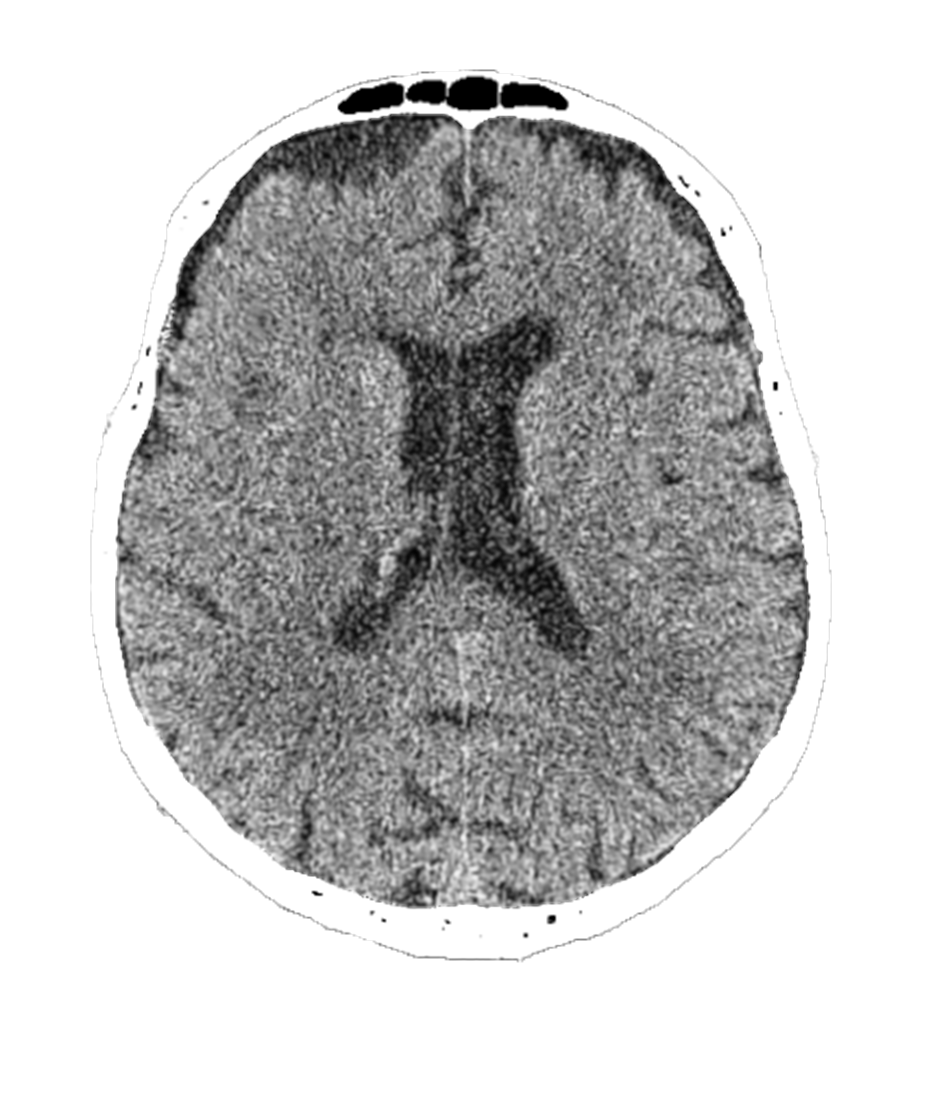

Virtual CT Perfusion

Our technology leverages advanced deep learning to generate perfusion maps directly from non-contrast CT scans. By eliminating the need for traditional perfusion CT, we enable faster, simpler, and more accessible stroke triage. Clinicians gain rapid insight into brain blood flow and tissue viability—helping them make critical treatment decisions when every minute counts.